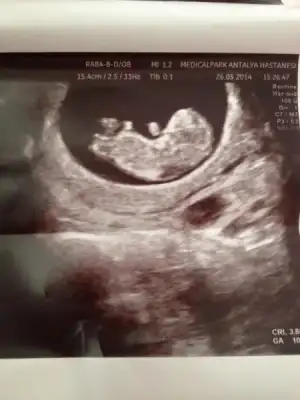

Dr tahmin etti kızlar :) sizce ne benim kuzum:)